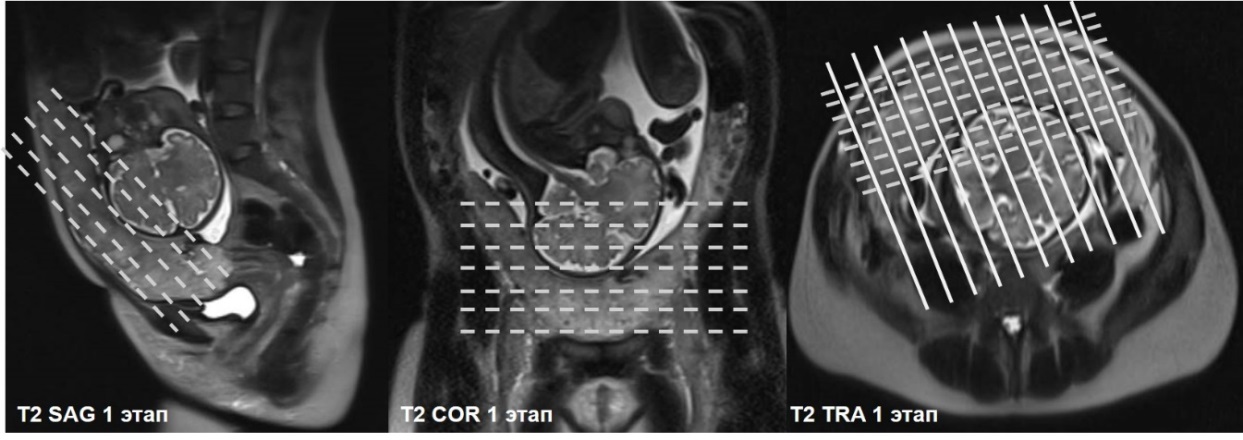

Первичный, или «материнский» этап, длительностью 3–5 минут, при котором получаемые Т2-ВИ многоплоскостные ортогональные МР-изображения (рисунок 1) ориентируются согласно анатомии беременной; целью его является оценка сегментарного расположения плацентарного диска в полости матки, контуров и размеров матки.

|

|

|

| А | Б | В |

| Рисунок 1 – Беременность 36 нед. МРТ плаценты. Первичный, «материнский» этап исследования. Т2 ВИ в сагиттальной (а), корональной (б) и аксиальной (в) плоскостях | ||